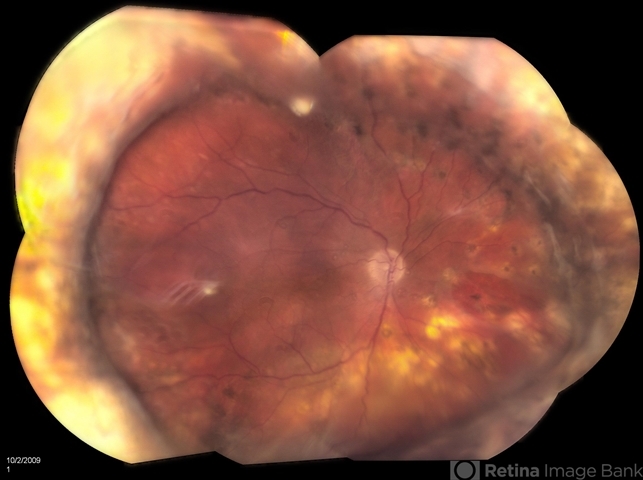

- retinal tear, dislocated posterior chamber intraocular lens (PCIOL)

- Jason S. Calhoun, Mayo Clinic Jacksonville, Florida

- Fundus camera

- 47-year-old male who had trauma to the right eye. Patient had retinal detachment surgery in the past (scleral buckle), to the right eye. Patient came in with another retinal detachment with dislocated PC IOL lens. Notice the haptics tearing the retina. Patient underwent vitrectomy with gas exchange. VA was hand motion 1 day post-op.